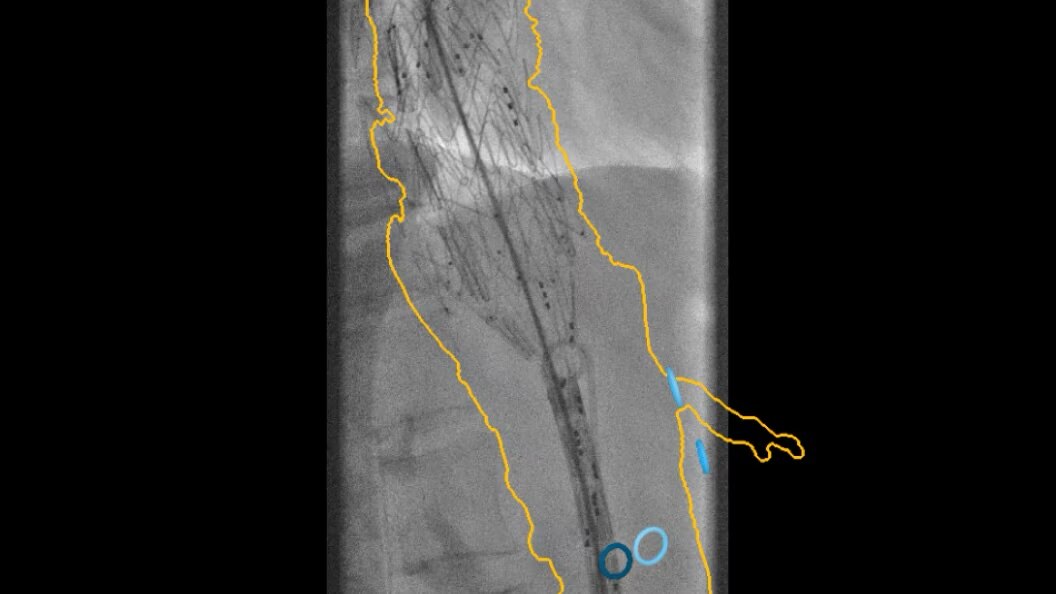

evar-assist-2-tile-en

EVAR ASSIST

Perform endograft procedures in one go with intuitive tools and a simplified workflow - less radiation, more efficiency